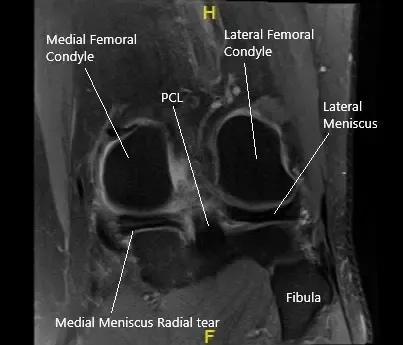

MRI of the left knee in the coronal section showing the torn medial meniscus.

MRI of the left knee suggested a tear of the posterior horn medial meniscus, notably with a radial component within the inner third, with meniscal extrusion into the medial gutter. There is tri-compartmental arthrosis, most pronounced over the patellofemoral compartment. Tendinosis of the extensor mechanism. Semimembranosus insertional tendinosis.